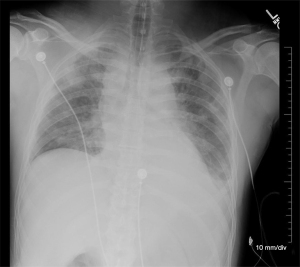

Chest X-ray after intubation confirmed proper tube placement with the endotracheal tub tip 5cm above the carina, and also showed central venous congestion with mild to moderate interstitial markings and a small left pleural effusion. Also noted were scattered ill-defined opacities of the right upper lobe. “CT examination for further evaluation if clinically indicated” was recommended (Figure 1). Scattered pulmonary nodules observed on CT-A of the thorax done previously were not noted on chest-X-ray.